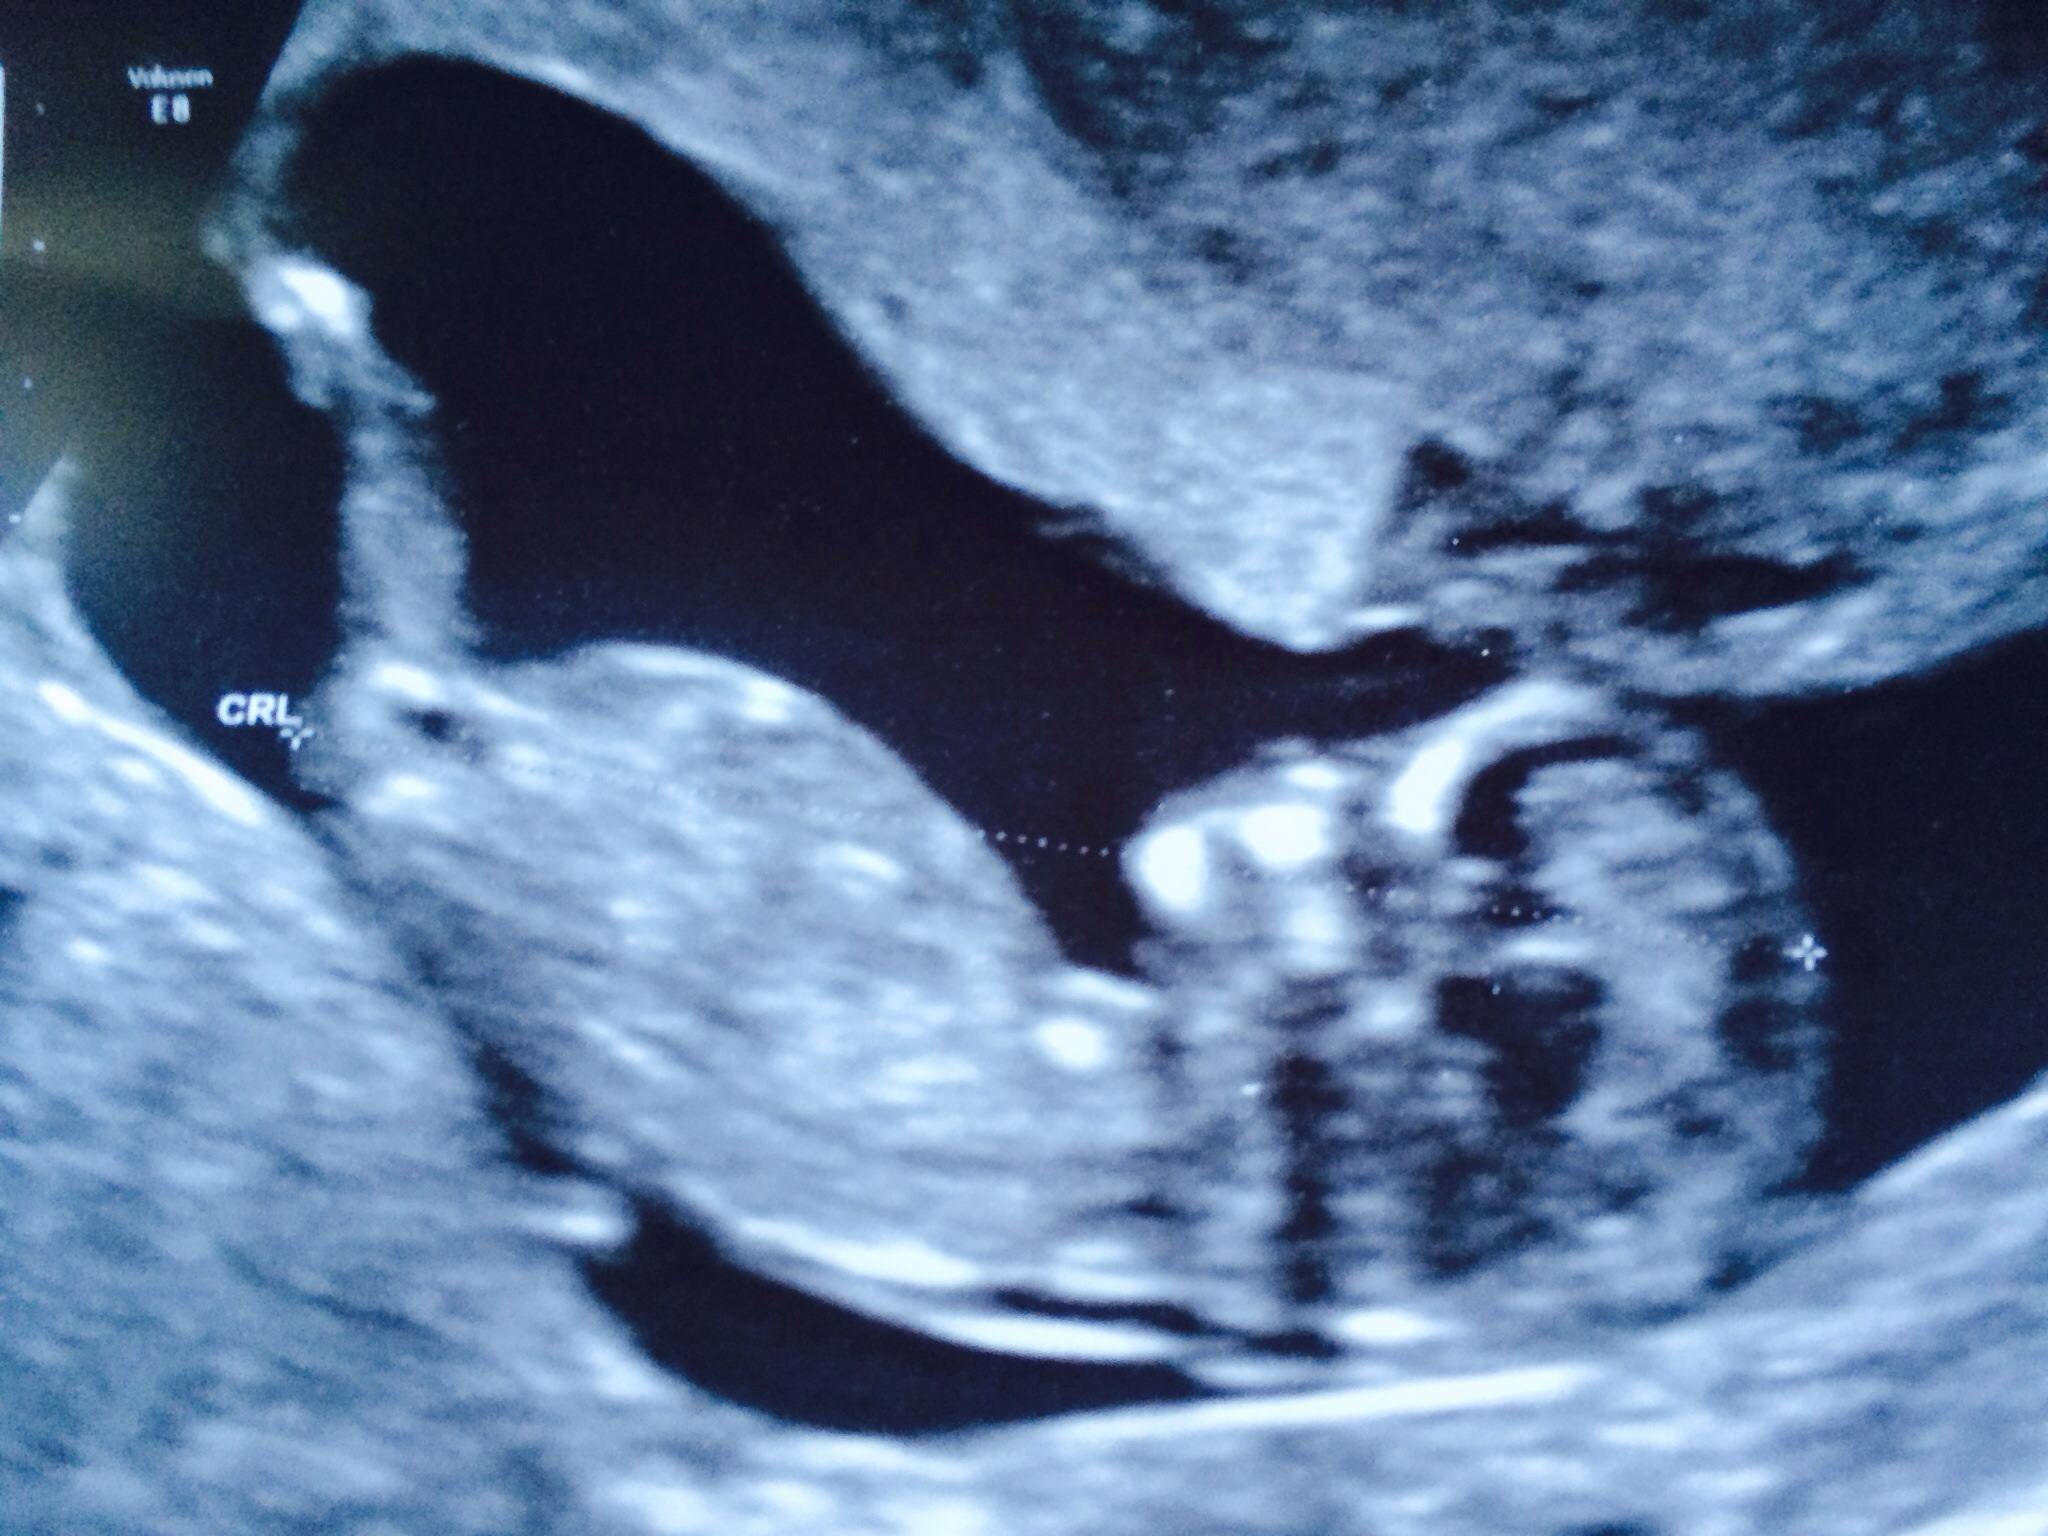

This was taken at 11w6d and I am not an expert so I am not sure if this is even a nub.

Thank you in advance for looking.

I don't see a nub. And it's a tad early on top of that. Not impossible to guess with the right shot. But comes with a caution that it could change. Any other pics?

Thanks for looking hotdogz. No other pics from down there. I wasn't sure it was a nub and I know it's early. I just didn't know what that line is in front of the leg, cord maybe, I am clueless. I am pretty sure its a boy anyway.

There is certainly nothing that screams boy from this pic :) You still have plenty of hope! Sorry I couldn't offer a guess.

Leg is blocking. Great, clear photo!

from the skull i would guess boy just a guess though

girl